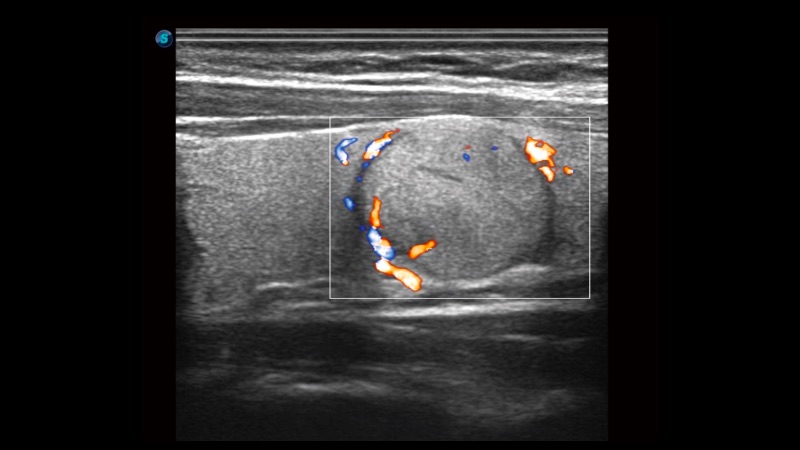

凸陣、線陣和相控陣探頭進(jìn)行實(shí)時(shí)掃描時(shí),開(kāi)啟擴(kuò)展成像模式,可以擴(kuò)展超聲圖像視野,以便更完整地查看大的病灶或組織器官的解剖結(jié)構(gòu)。

通過(guò)色彩血流和實(shí)時(shí)寬景相結(jié)合,可觀察到完整的靜脈或動(dòng)脈的血流,方便醫(yī)生檢查。實(shí)時(shí)掃查過(guò)程中,如有任何操作失誤也可以很容易地進(jìn)行回掃擦除,而不會(huì)中斷掃查。